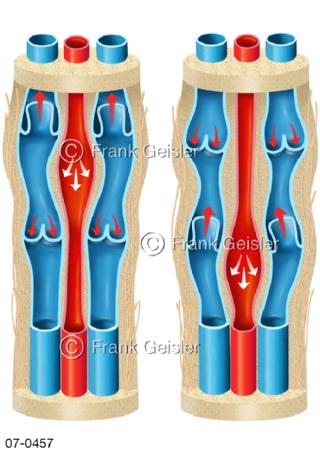

Bildergalerie Herz, Blutkreislauf

Bilder zu Herz, ein muskuläres Hohlorgan, das den menschlichen Körper durch rhythmische Kontraktionen mit Blut versorgt und dadurch die Durchblutung der Organe sichert, das Kreislaufsystem zeigt den Transport von arteriellem sowie venösem Blut durch das kardiovaskuläre System (Herz-Kreislauf-System), bestehend aus Blutgefäßen, Lymphgefäßen und dem Herz